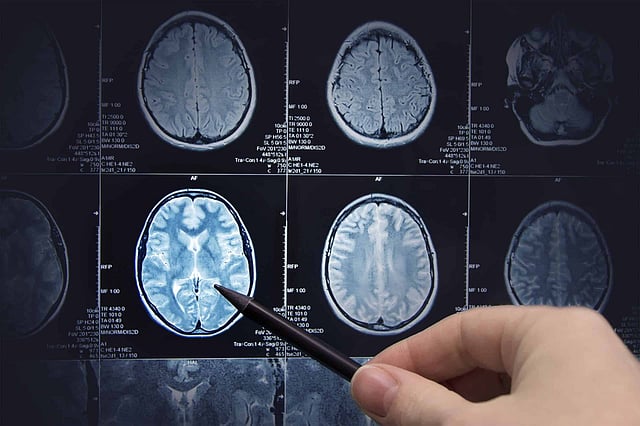

Brain research, magnetic resonance imaging

Magnetic Resonance Imaging uses a large magnetic radio wave to create a detailed cross-sectional image of internal organs and structures. An MRI scanner contains two powerful magnets.

The magnetic field can then aid in producing cross-sectional images of any part of the body. It is used for detecting the anomalies of the brain and spinal cord, tumours, cysts, breast cancer, knee or joint injuries, heart and liver anomalies and others.